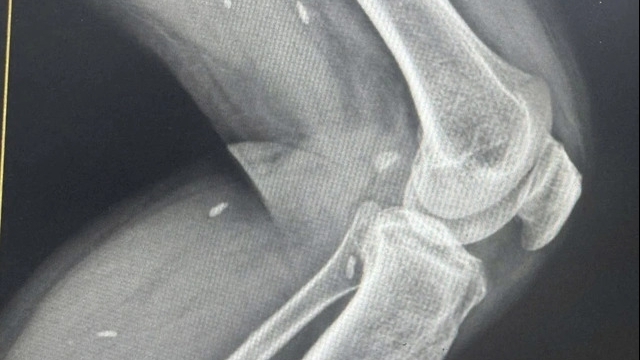

Với 12 ngày điều trị tích cực bằng nỗ lực không biết mệt mỏi của các bác sĩ, tình trạng của bệnh nhân mới cải thiện dần. Bệnh nhân được rút ống thở máy và tự thở oxy. Đặc biệt, tình trạng suy đa tạng được kiểm soát tốt, sinh hiệu ổn định, bệnh nhân tỉnh táo, giao tiếp tốt với các y bác sĩ điều trị.

| Sau khi được cấp cứu, điều trị tích cực, bệnh nhân N.Q.T đã tỉnh, tiếp xúc tốt, sinh tồn ổn định |